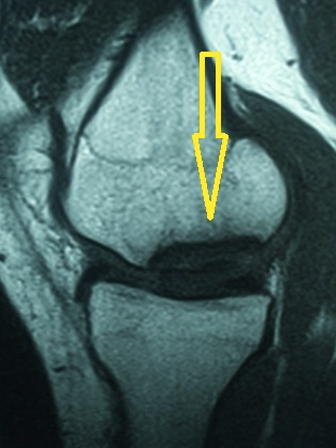

18 yaşında erkek hasta, profesyonel basketbol oyuncusu.

Uzun süredir devam eden diz ağrıları, maç sırasında gelişen burkulma ile artmış. Dizde şişme, ağrı ve basamama şikayetleri ile başvurdu. MR tetkikinde eklem hattında kıkırdak ve kemik içeren büyük bir eklem faresinin serbestleştiği görüldü (Gr 3 Osteochondritis Dissecans)

Hastanın ayrışmakta olan kıkırdak hattı kendi dizinin diğer alanlarından alınan kemikli kıkırdak tüpleri ile artroskopik olarak tespit edildi. (Mozaikplasty Plug Tespiti) Böylece hem ayrışmakta olan kıkırdak tespit edildi hem de ayrışma bölgesi taze kemik ve sitokinlerle tekrar kaynamaya zorlandı.